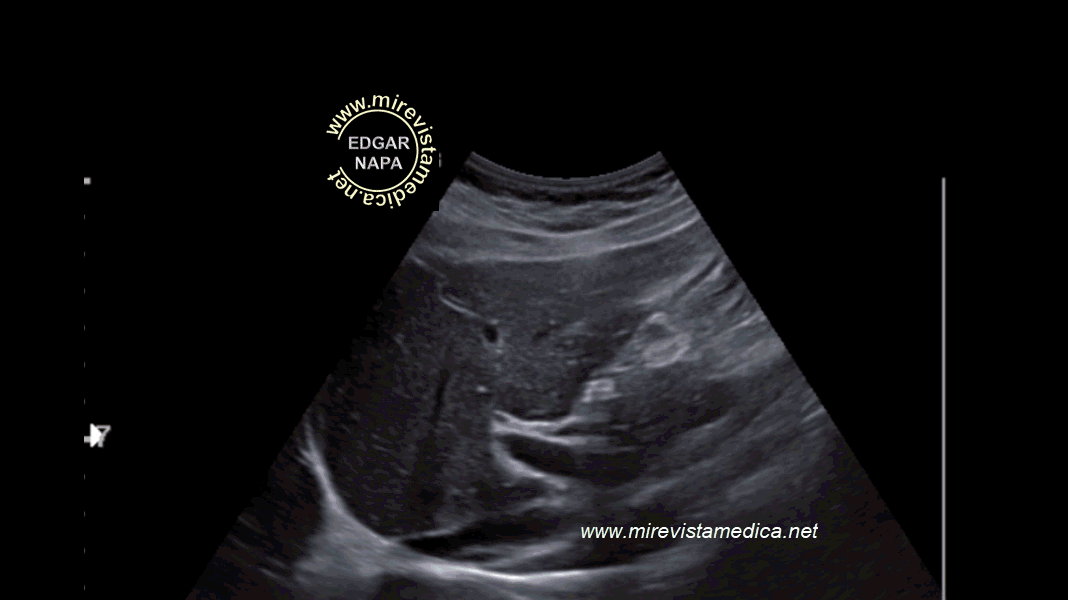

Anatomía imagenológica de la vía biliar